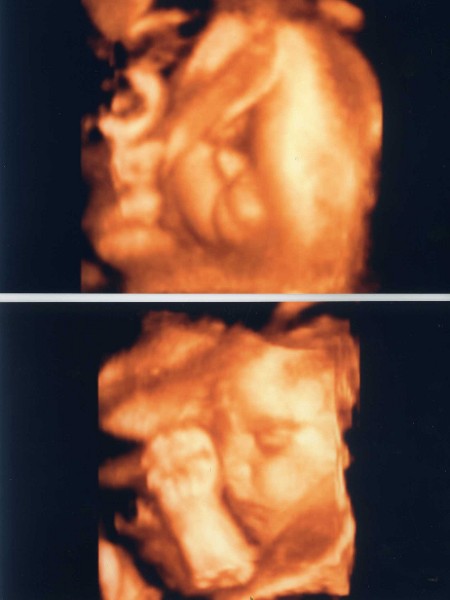

Tegnap voltam uh-án, Minden ok Marcussal, már 1381g, és korának teljesen megfelelő. szégyenlős még mindíg. De sikerült pár kép róla, és arról is hogy tuti fiú. Teszek is fel róla két képet, remélem ez nem számít pornográfnak.

Íme a képek: Kép

Nagyon édes Marci baba, szépen látszik az arcocskája.